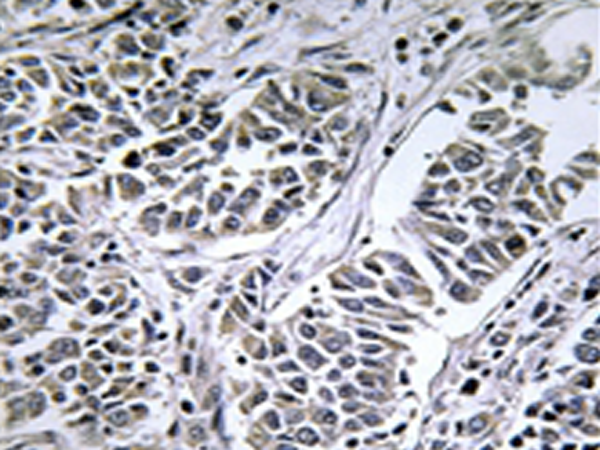

IHC positive control: |

Human lung carcinoma tissue |

IHC Recommend dilution: |

50-100 |